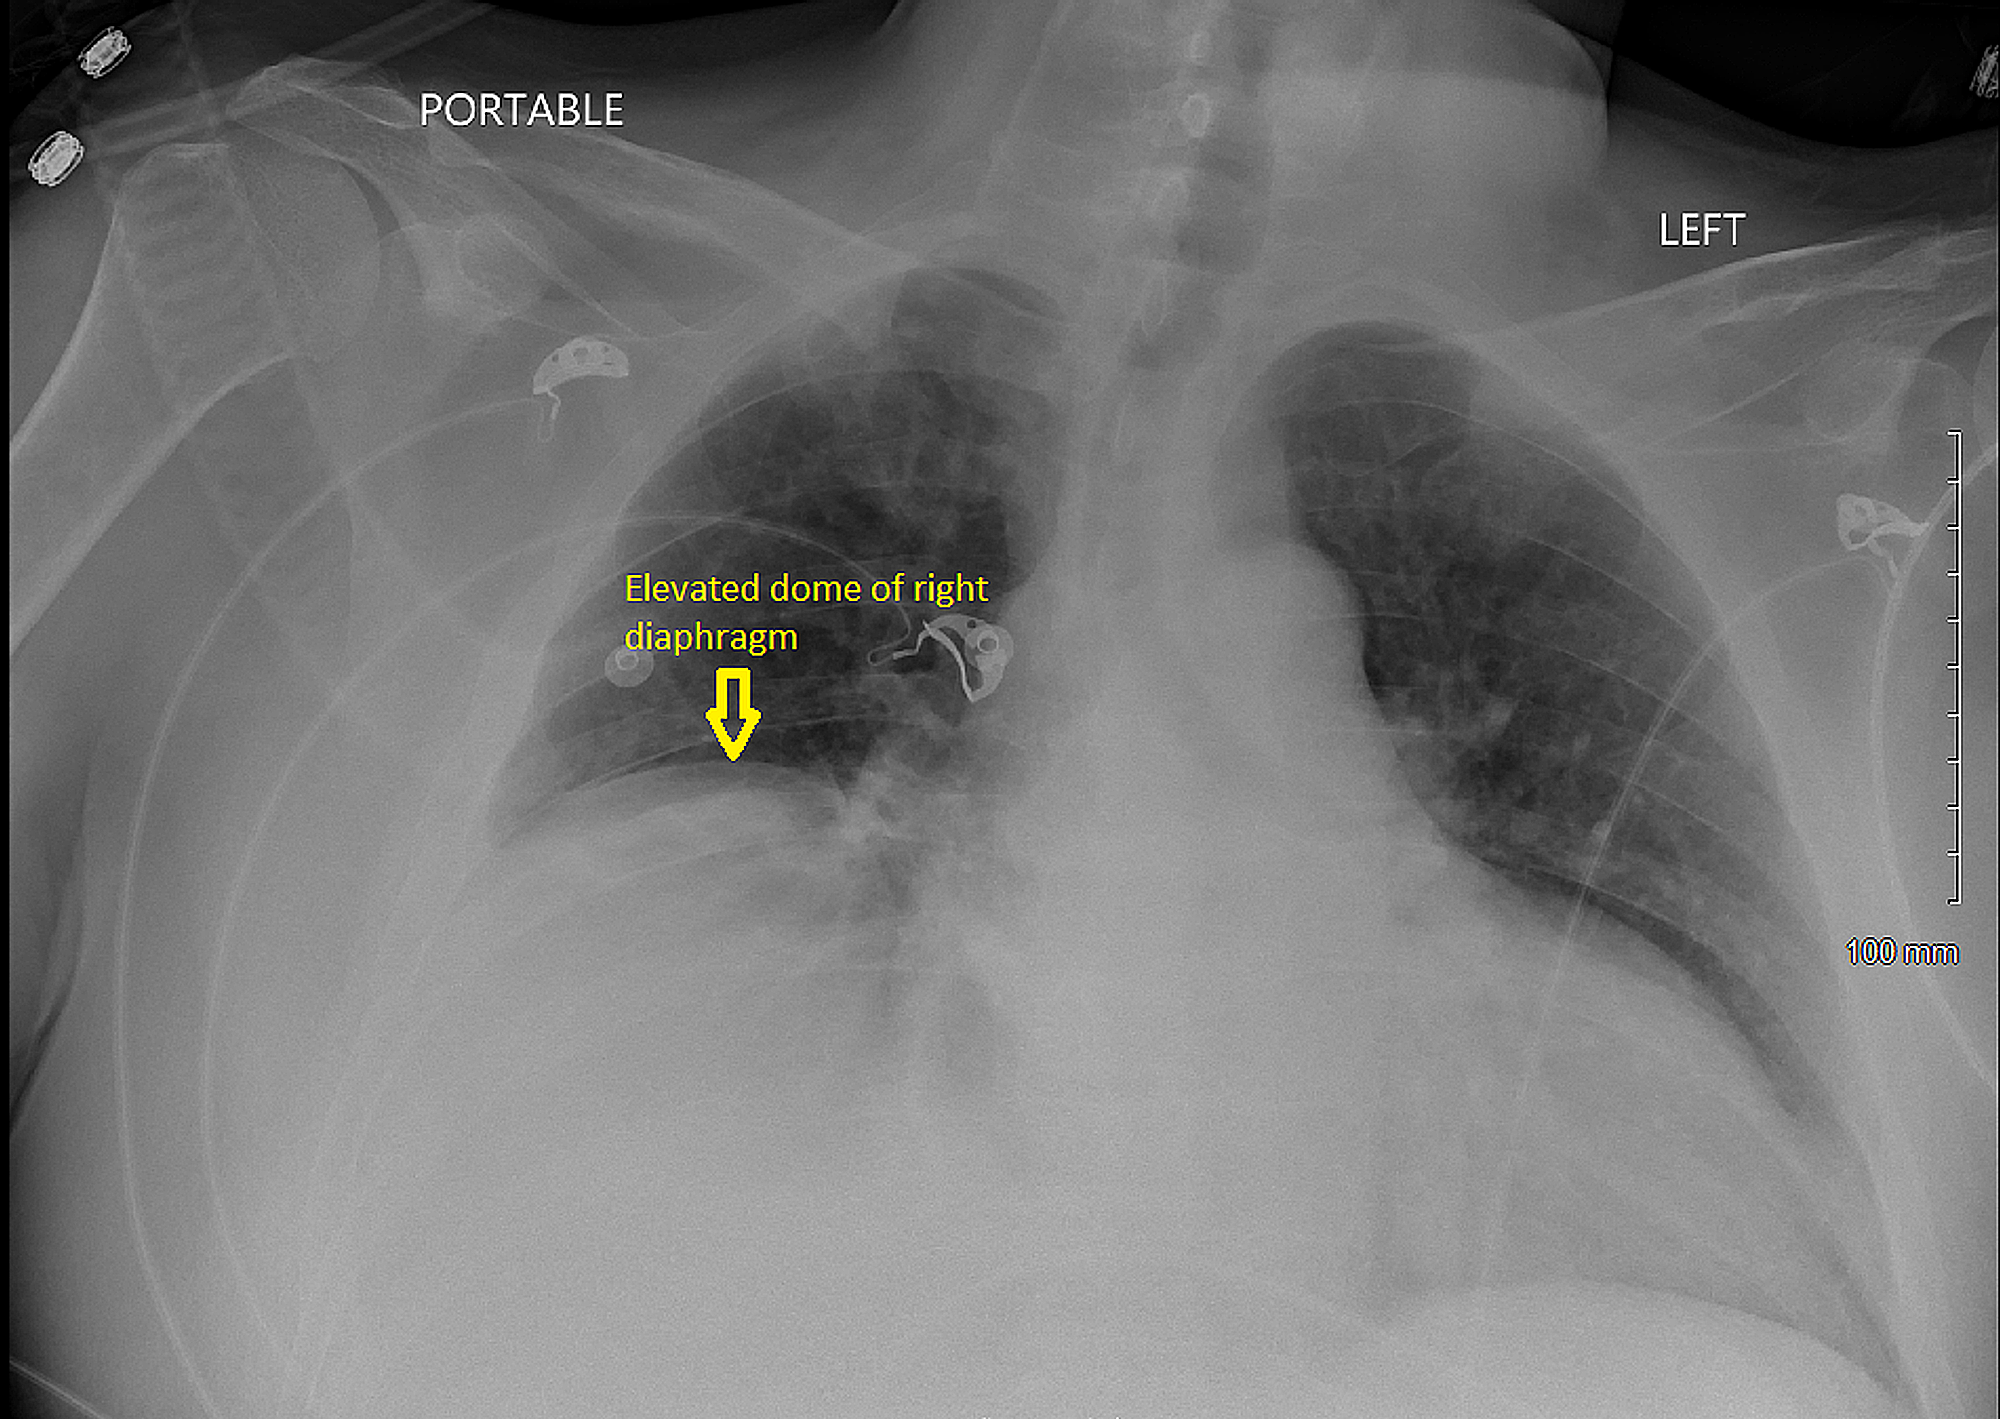

Pneumoperitoneum and subphrenic abscess are two important differential diagnosis of this radiographic sign which can be excluded out when normal plicae circulares or haustral markings of the colon is seen under the right diaphragm. If youre experiencing mild discomfort in your diaphragm take a few minutes to concentrate on deep breathing. Treatment depends on the type of hiatal hernia you have and on your symptoms.

Place one hand on your abdomen and breathe deeply. Reduced number of alveoli air sacs required for normal breathing. In severe cases when there is no simple treatment that can relieve dyspnea your doctor may prescribe morphine. Congenital diaphragmatic hernia CDH. There is usually a long history of heavy smoking. Shortness of breath may be accompanied by wheezing. Diaphragmatic dysfunction caused by transverse myelitis or leukemic infiltration of the cervical spinal cord in a patient with leukemia and shortness of breath. To treat phrenic nerve irritation This condition can be managed with a breathing pacemaker which takes over the responsibility of sending messages to the diaphragm. The cause for shortness of breath was thought primarily due to stable angina on tread mill test positive finding but Chilaiditis syndrome should also be considered as a cause for the shortness of breath.